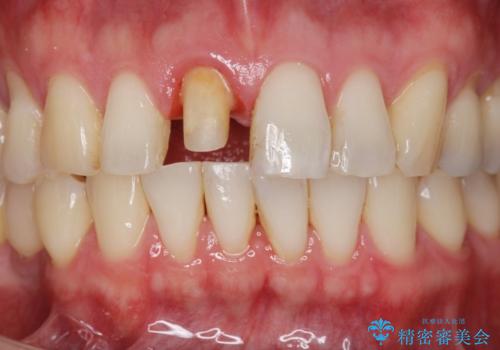

前歯の変色を改善 オールセラミック治療

- 目立つ前歯の変色の改善を希望され来院されました。

根管治療を行いそのままにしていると歯は、徐々に変色を来します。

感染の疑われる根管内に対し再度根管治療を行い、セラミッククラウンを作製することで審美性の回復します。